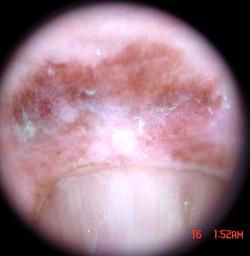

{

"age_approx": 65,

"anatom_site_general": "upper extremity",

"anatom_site_special": "acral NOS",

"concomitant_biopsy": true,

"dermoscopic_type": "contact non-polarized",

"diagnosis_1": "Malignant",

"diagnosis_2": "Malignant melanocytic proliferations (Melanoma)",

"diagnosis_3": "Melanoma in situ",

"diagnosis_confirm_type": "histopathology",

"family_hx_mm": false,

"image_type": "dermoscopic",

"mel_thick_mm": "0.00",

"melanocytic": true,

"patient_id": "IP_3069248",

"personal_hx_mm": false,

"sex": "male"

}